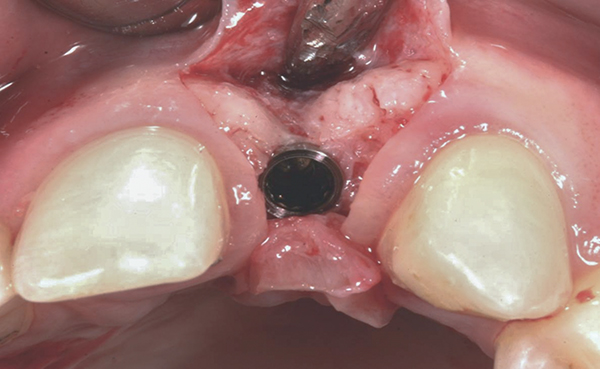

Fig 7. Vertical releasing incisions sutured to attain primary closure, buccal view.

Figure 7